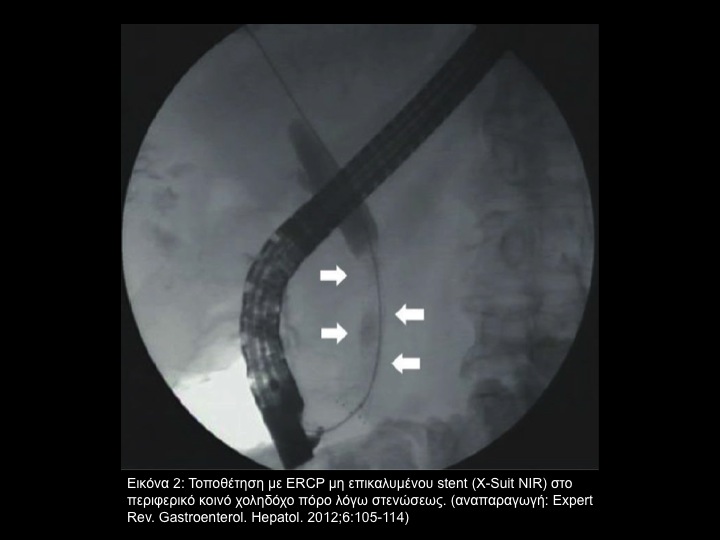

Η ενδοσκοπική παροχέτευση χολής τρεχόντως είναι η standard επιλογή στην απόφραξη των χοληφόρων με ανακουφιστική πρόθεση. (Εικόνα 1), (Εικόνα 2)